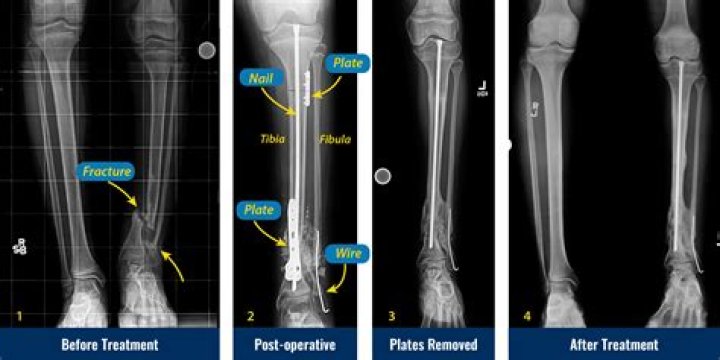

Congenital Pseudoarthrosis Treatment by Paley Cross Union Protocol

What is tibial pseudarthrosis?

Tibial pseudarthrosis is the name given to a fracture of the tibia (the larger of the two bones in the lower leg) that does not heal correctly.